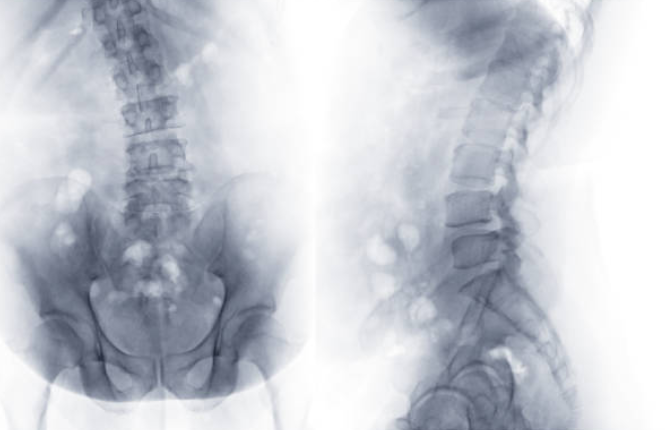

척추측만증

허리통증의 원인 중 척추측만증이 있습니다. 척추는 정면에서 보았을 때 일자로 곧게 뻗어야 정상이지만, 옆으로 구부러지면 척추측만증이라고 합니다.

등 부위에 뒤로 나온 굴곡이 지나치게 심해지면 꼽추라고 표현하는 척추기형이 발생합니다. 척추가 굽는 것을 척추측만증이라고 합니다.

허리디스크란?

허리디스크는 척추 뼈 사이에 있는 디스크가 손상되어 신경을 압박하는 질환입니다. 디스크는 척추뼈 사이의 충격을 흡수하고 척추의 움직임을 부드럽게 해주는 역할을 하는데, 이 디스크가 손상되면 신경을 압박하여 통증, 마비, 감각 이상 등의 증상이 나타납니다. 허리디스크는 흔히 40~50대 중년층에서 발생하지만, 젊은 나이에도 발생할 수 있습니다.